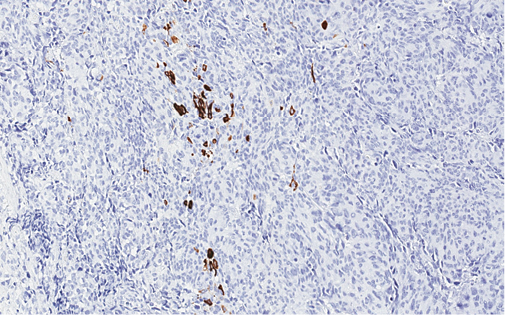

4 pav. Tik imunohistocheminiais metodais (MUC2) identifikuojama abortyvi mucinų produkcija pavienėse naviko ląstelėse

Imunohistocheminio profiliavimo metu nustatyta stipri difuzinė PanCK reakcija visuose komponentuose (3 pav.) ir menka, tačiau definityvi MUC2 žarninio tipo mucinų produkcija (4 pav.) kartu su tipiška KRAS geno 12-o kodono mutacija 2-ame egzone leistų klasifikuoti naviką kaip aukšto laipsnio (blogai diferencijuotą) adenokarcinomą. Ieškant biologinio pagrindo neįprastai naviko morfologijai paaiškinti atliktos papildomos imunohistocheminės reakcijos: Hep-Par1 (neigiama), INI1 (praradimo nėra), BRAF (neigiamas, tikėtina, nemutuotas), PMS2 ir MSH6 (reakcija išlikusi, nėra mikrosatelitų nestabilumo audinyje požymių), visose naviko ląstelių populiacijose patvirtintas jau biopsijoje identifikuotas difuzinis neuroendokrininis fenotipas (100 % Synaptophysin ir 95 % Chromogranin A ekspresija (5 pav.)). Ki67 proliferacinis aktyvumas buvo heterogeniškas ir rabdoidinės išvaizdos komponente siekė 90 proc., o likusiuose buvo perpus žemesnis (6 pav.).